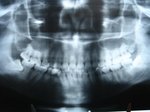

智歯なのに頭が悪い?(2) 親知らず 前回の症例では同一個体では同じように反対側の親知らずも7番を吸収しつつあるので予防のため抜歯を行いました。 関連記事 水平埋伏智歯の抜歯例上の歯は痛くないけど下の抜歯は痛い下の親知らずが痛いのに上を抜かれちゃった親知らずが下歯槽神経圧迫智歯歯肉弁除去水平埋伏智歯 投稿ナビゲーション 智歯なのに頭が悪い?(1)